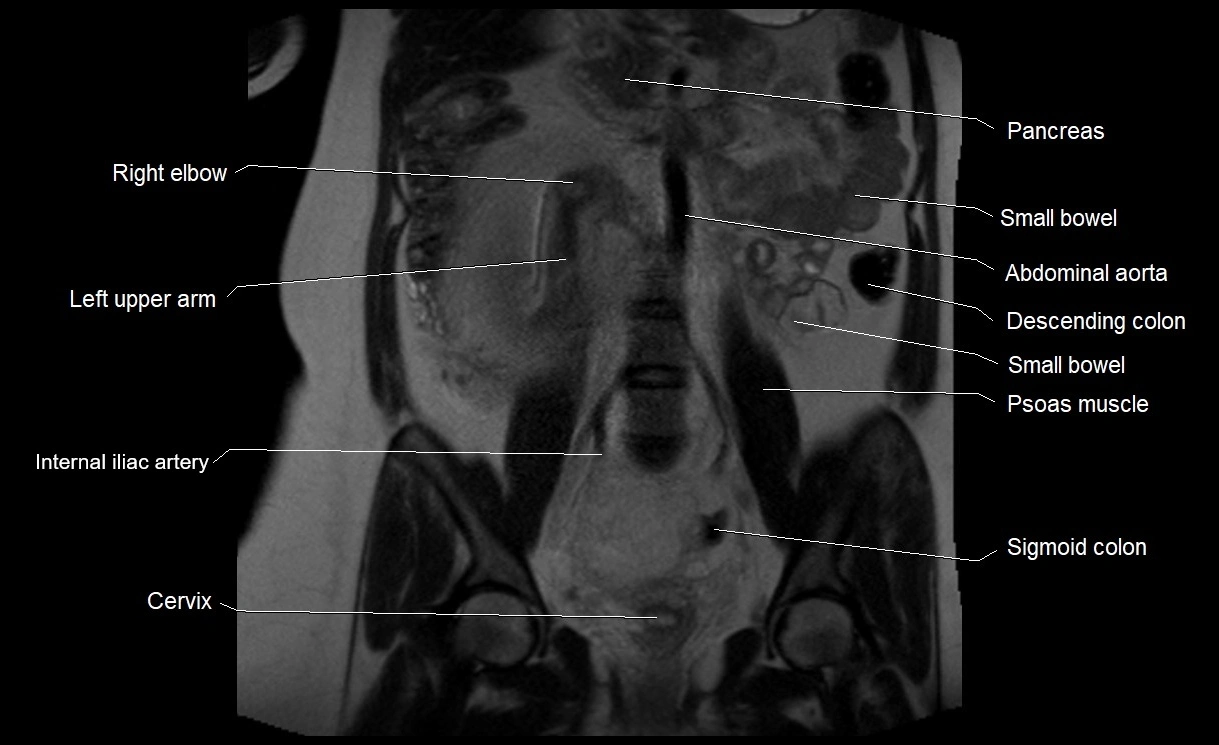

MRI Appearance

T2 HASTE (T2 GRE):

• Amniotic fluid shows very bright hyperintense signal

• Provides natural contrast against fetus and placenta

• Small particles (vernix) may appear as scattered hypointense foci within bright fluid

T1 GRE:

• Amniotic fluid shows low signal intensity (dark)

• Hemorrhage, infection, or proteinaceous content may cause focal or diffuse high signal intensity

MRI image

image